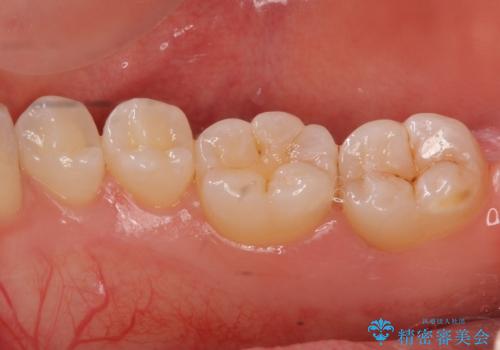

奥歯の虫歯 セラミックインレーによる治療

- 検査をしたところ奥歯に小さな虫歯を発見。

大きくなる前に白い詰め物で治療がしたいとのことでセラミックインレーでの治療になりました。

口の中を見ただけでは異常がないのにレントゲン画像上では虫歯がある、といったことは多々あります。奥歯とはいえ、口をあけると外から見えてしまうため白いセラミックでの治療ができたことを大変喜んでいただけました。